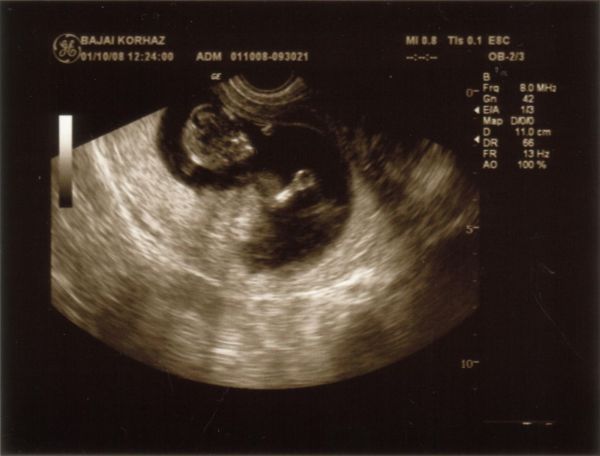

11-re mentünk a MÁV-ba, mikor rámkerült a sor csináltak egy UH-t.

Megnézték hol a baba és mondták minden mondanak majd..

Én hol a plafont hol a babát néztem, esküszöm olyan volt mint ha a baba ahogy ugrál hozzáér a tűhöz...

Én is tudom, hogy biztos a baba jól van, mert utánna is mutatták ahogy mocorog és dobog a szíve, de egyszerűen nagyon rossz érzés volt...biztos hülyeség hogy a tűt láttam körülötte....

Ismerjétek meg a kisfiam

Ismerjétek meg a kisfiam